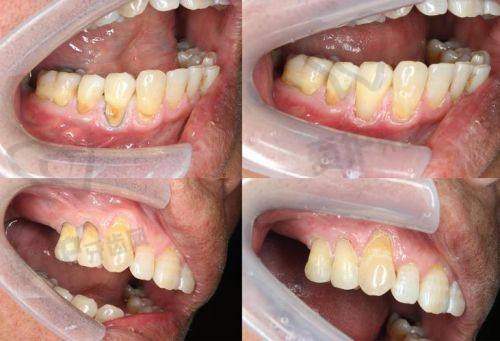

3M树脂250使用的是微米级复合树脂,其填料颗粒约40nm。这种材料是比较早的复合树脂类型。而3M树脂350采用的是纳米级树脂,填料颗粒约20nm。纳米级树脂的优势在于其材料更加细腻,这使得它在抛光后能呈现出更好的成效。相比之下,3m250的材料细腻程度不如350,在一些对表面光滑度和美观度要求较高的情况下,350会更具优势。

硬度方面,3m250的硬度相对较低,而3m350硬度较高。这意味着3m350能更好地承受咀嚼压力。在日常生活中,我们的牙齿需要不断咀嚼食物,承受各种压力。如果补牙材料硬度不够,就容易出现磨损甚至损坏的情况。3m350的高硬度使其更适合用于需要承受较大咀嚼力的区域,比如后牙。

耐磨性上,3m250的耐磨度较弱,长期使用后可能会出现色素沉积或颜色变化,边缘着色的概率也相对较高。而3m350的耐磨性更优,能够在较长时间内保持良好的状态,减少因磨损导致的问题,也能更好地维持牙齿的美观。

美观度是特别多人在补牙时非常关注的一点。3m350在这方面表现出色,它的色泽更接近自然牙,并且提供四大色系36种颜色选择。患者可以根据自己牙齿的实际颜色选择更匹配的材料,从而达到几乎与自然牙无异的成效。而3m250的色泽较暗沉,颜色匹配范围有限,在美观度上稍逊一筹。对于前牙修复,美观度尤为重要,因为前牙直接影响到我们的面部外观和笑容。在这种情况下,3m350可能是更好的选择。

3m250适用于前牙小范围缺损或浅龋修复,它注重经济性。对于一些较小的牙齿问题,使用3m250既能解决问题,又能控制成本。而3m350适用于后牙大缺损或深龋修复,尤其适用于需要承受咀嚼压力的区域,它兼顾了美观与耐用性。后牙在咀嚼过程中承担着重要的任务,需要更坚固、耐磨的材料,3m350正好满足了这些需求。

选择3m250还是350,需要结合多方面因素考虑。首先是牙齿缺损的位置和大小,如果是前牙小范围缺损,且注重经济性,3m250是不错的选择;如果是后牙大缺损或深龋,需要承受较大咀嚼压力,那么3m350更合适。其次是预算,如果预算有限,3m250能在一定程度上满足需求;如果预算充足,追求更好的性能和美观度,3m350会带来更好的体验。末尾,一定要听取医生的建议,医生会根据患者的具体口腔情况和需求,给出更专精的选择。